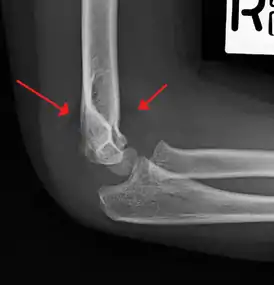

| An elbow X-ray showing a displaced supracondylar fracture in a young child | |